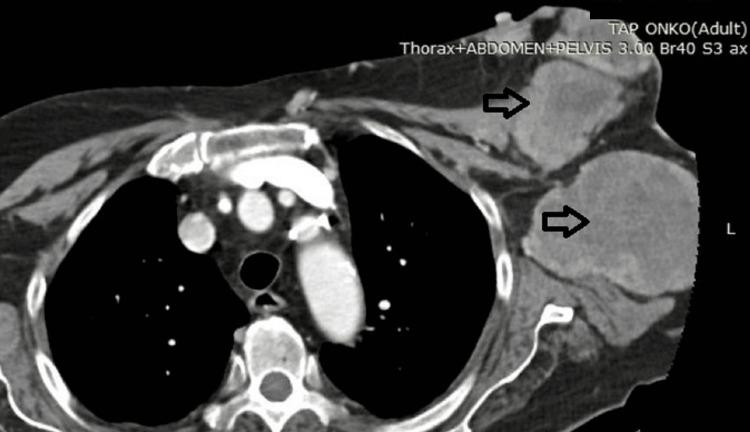

手术挽救策略:应对胸壁肉瘤急症

Soft tissue sarcomas arising from the chest wall are an extremely rare entity. They are classified as mesenchymal tumors of varying aggression. It is this unpredictable behavior that makes them an unexpected hurdle even for experienced surgeons. Given the intricate anatomy of the thorax, any of its various tissues can potentially give rise to a sarcoma. Soft tissue sarcomas, in particular, present a diagnostic and surgical difficulty due to the necessity of complex surgical techniques and the rising need for chest wall reconstruction. These tumors are the subject of multidisciplinary discussions to come to the best therapeutic course. This is precisely what will prevent recurrence and ensure a better understanding of this pathology. In this report, we present the case of a recurrent soft tissue sarcoma that required emergency surgery due to spontaneous bleeding. It perfectly showcases the complicated treatment of such pathologies and is of profound surgical interest as it utilizes a large chest wall resection, coupled with an intricate subcutaneous flap reconstruction. In this report, we tried to outline the critical aspects of sarcoma surgery and presented our method of choice when reconstructing the soft tissues of the chest.

起源于胸壁的软组织肉瘤是一种极为罕见的疾病。它们被归类为具有不同侵袭性的间充质肿瘤。正是这种不可预测的行为,使得即使对于经验丰富的外科医生来说,它们也是一个意想不到的障碍。鉴于胸部复杂的解剖结构,其任何一种组织都有可能引发肉瘤。特别是软组织肉瘤,由于需要复杂的手术技术以及对胸壁重建的需求不断增加,呈现出诊断和手术上的困难。这些肿瘤是多学科讨论的主题,以确定最佳治疗方案。这恰恰能防止复发,并确保对这种病理状况有更好的理解。在本报告中,我们介绍了一例因自发性出血而需要紧急手术的复发性软组织肉瘤病例。它完美地展示了此类病症的复杂治疗过程,并且由于采用了大面积胸壁切除以及复杂的皮下皮瓣重建,具有深远的外科研究价值。在本报告中,我们试图概述肉瘤手术的关键要点,并介绍我们在重建胸部软组织时所选择的方法。